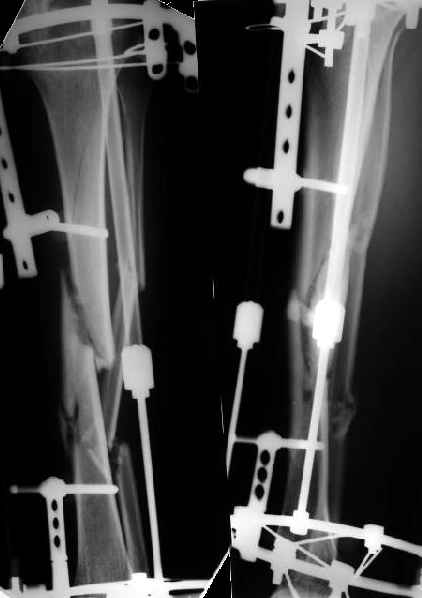

Диагноз: двойной оскольчатый перелом правого бедра в с/3 и н/3 со смещением, открытый оскольчатый перелом правой большеберцовой кости в с/3 со смещением двойной перелом малоберцовой кости. Оперирован проведена открытая репозиция, остеосинтез двумя пластинами бедренной кости, иммобилизация кокситной повязкой. На контрольных рентгенограммах от 21 01 04 имеется: несостоятельность остеосинтеза бедренной кости в в/3 выраженная угловая деформация; консолидирующийся перелом большеберцовой кости со смещением по длинне и выраженной вальгусной деформацией. Родственникам рекомендовали оперативное лечение. Больного доставят на осмотр 28.01.04, обдумываем способы лечения. Оперативное лечение планируем в два этапа, вначале на бедре, затем на голени. На бедре- удаляем верхнюю пластину, проводим остеотомию по линии верхнего перелома, проводим репозицию, остеосинтез пластиной с фиксацией верхнего, среднего и нижнего фрагментов.На голени-мнения разделились:- можно наложить аппарат внешней фиксации на голень, провести остеотомию б/берцовой кости в зоне перелома между проксимальным отломком и осколком, остеотомию малоберцовой кости, провести постепенную репозицию, тибиализацию (рисунок 3).-или провести остеотомию по линии перелома большеберцовой кости, репонировать и фиксировать пластиной. Новосибирская областьг Куйбышев ЦРБСергей Зырянов

Как я уже сообщал, пациент поступил к нам в пятницу на прошлой неделе.

Ко всему прочему у него еще и разгибательная контрактура коленного сустава - амплитуда градусов 15.

Сегодня сделана операция. Из бедра минимально инвазивно удалены пластинки. Один винт на верхней пластинке оказался сломан, так что пришлось там сделать разрезик побольше, см 5.

Хотя и с трудом, но на бедре удалось сразу выполнить закрытый интрамедуллярный остеосинтез с минимальным рассверливанием.

Редрессацию колена даже пытаться делать не стали.

На голени - чрескожная остеотомия малоберцовой кости, закрытая остеоклазия большеберцовой, дистракционный остеосинтез аппаратом.

В плане - востановление длины и оси голени, разработка движеий в колене. Не уверен, что удастся синтезировать голень стержнем при таком маленьком сгибании в коленном суставе.